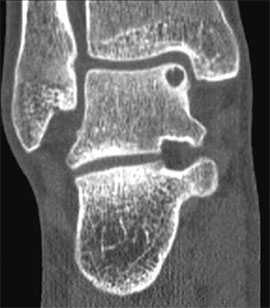

На КТ определяется остеохондральное повреждение таранной кости.

- для диагностики повреждений хряща и предоперационного планирования предпочтительно использование КТ;

КТ и МРТ

Для предоперационного планирования, однако, предпочтительно использование компьютерной томографии (КТ). КТ включает исследование с шагом 0,5 мм и ЗD реконструкцией поврежденного сустава. МРТ полезно для диагностики сопутствующих повреждений мягких тканей (мышц, связок и сухожилий).

Для того, чтобы оценить точные размеры и локализацию дефекта, обязательно проведение спиральной КТ.